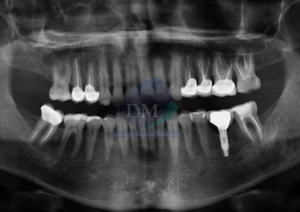

Paciente femenino de 16 años acude al Instituto de Diagnóstico Maxilofacial (sede Miraflores) para evaluación quirúrgica. Radiografia Panorámica A la evaluación de la radiografía panorámica